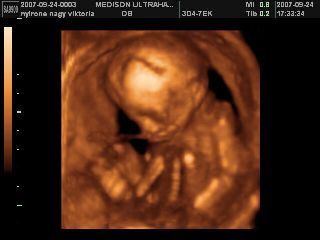

Na megjöttünk az uh-ról, 17 órára volt időpontunk, de majd fél órát csúszott a dolog, mert a doki később tudott bejönni! Minden rendben van, mindene magvan, annyi, amennyinek lennie kell, normál a szíve, a vesék rendben, gyomortelítődés van, méhlepény a fundusban, köldökzsinór 3 erű, viszont nem igen látszott, hogy milyen nemű! A doki szerint inkább lány, mint fiú, de egyáltalán nem mondta egyértelműre, és nem is látszott, összeszorította a lábacskáit a kis szégyenlős! :lol: De a lényeg az, hogy egészséges, és végre láttam az arcát is! :D